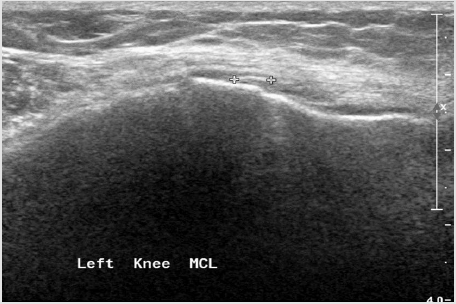

Figure 11: Medial collateral ligament partial tear - thickening, hypoechoic proximal part of the ligament with fluid around it.